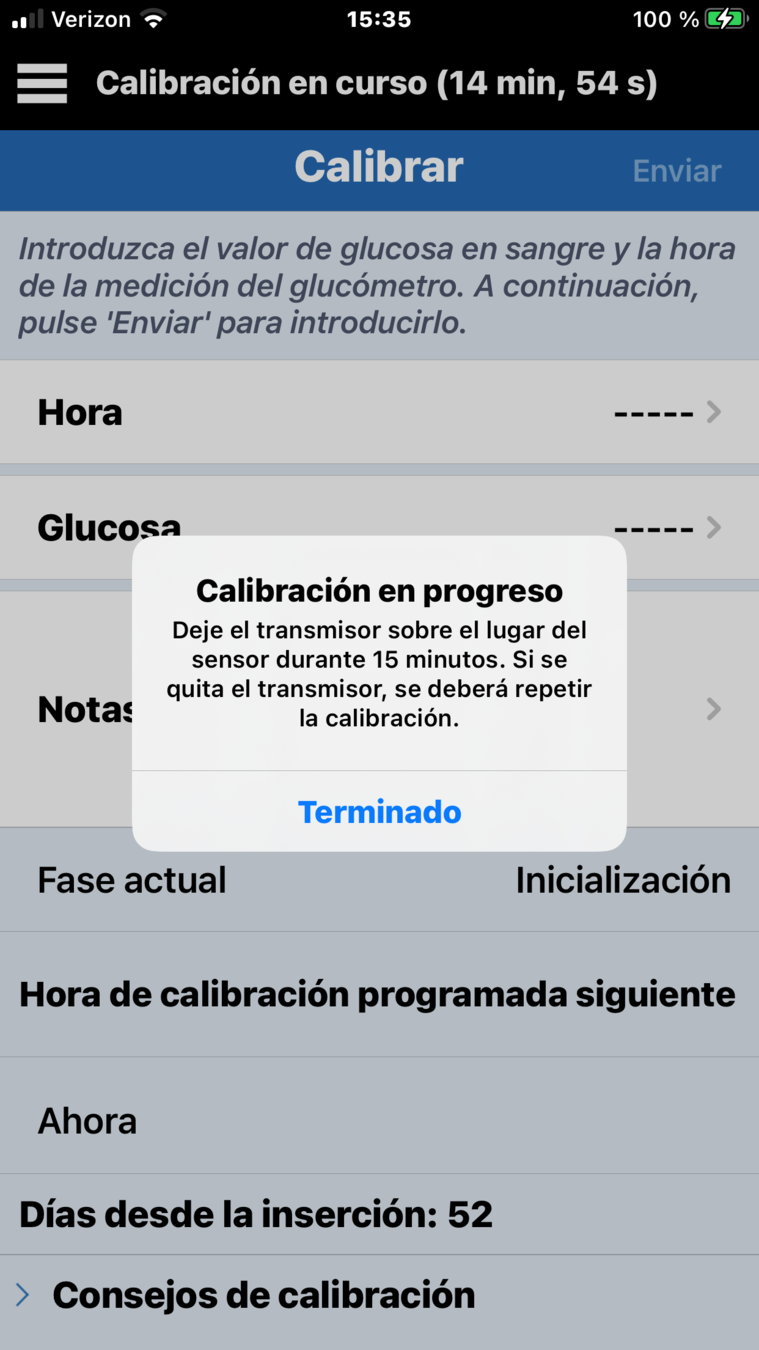

Para introducir una calibración, haga una comprobación de glucosa en sangre mediante punción capilar…

… y toque en el botón Calibrar.

INTRODUZCA UNA CALIBRACIÓN

Confirme que se han introducido los valores correctos de glucosa y, a continuación, toque Enviar.

Recibirá una notificación de Calibración en curso, que podrá borrar pulsando Terminado.

INTRODUZCA UNA CALIBRACIÓN

Por último, contar con una buena técnica de calibración es la mejor forma de garantizar la máxima exactitud del sistema de MCG Eversense® E3, por lo que a continuación ofrecemos algunos consejos de calibración.

CONSEJOS DE CALIBRACIÓN

- Lávese siempre bien las manos y séqueselas por completo.

-

No realice la calibración cuando

la glucosa pueda estar cambiando rápidamente, como después de comer, después de administrar

la insulina o durante el ejercicio

o después de él.

- Introduzca siempre un valor de glucosa en sangre real e introduzca la calibración antes de que transcurran 10 minutos desde la obtención de la glucosa capilar.

- Y, por último, mantenga el transmisor inteligente en su sitio encima del sensor Eversense® E3 durante al menos 5 minutos antes y 15 minutos después de cada calibración.

CONSEJOS DE CALIBRACIÓN